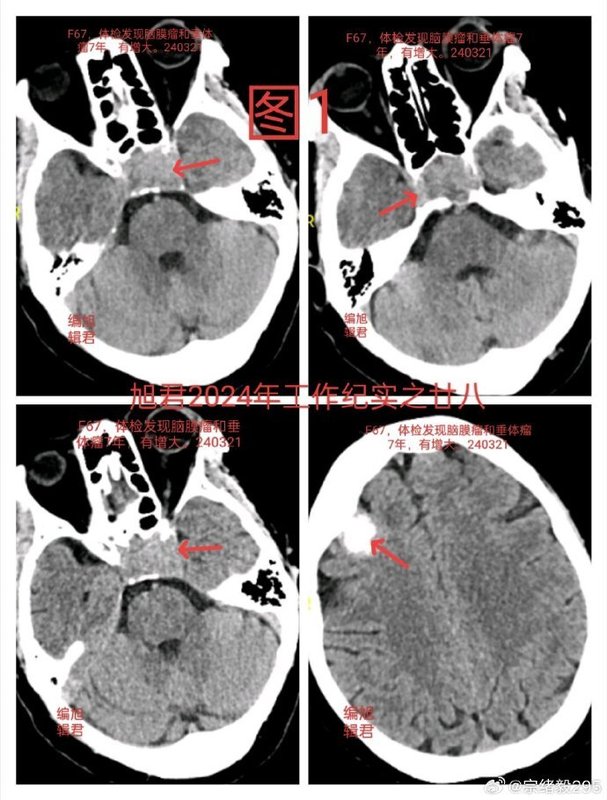

以案解析丨垂體腺瘤合并腦膜瘤處置策略

一位67歲的患者,7年前在體檢中通過MR和CT掃描發(fā)現(xiàn)垂體腺瘤合并額部小腦膜瘤。垂體腺瘤位于鞍內(nèi),無侵襲;額部腦膜瘤表現(xiàn)為明顯骨化。由于當時患者無明確臨床癥狀,因此選擇觀察隨診。近期復(fù)查結(jié)果:患者近期復(fù)查的MR和CT掃描顯示,垂體腺瘤仍位于鞍內(nèi),但比較之前略有增大,不過左側(cè)出現(xiàn)輕微侵襲海綿竇的跡象;額部腦膜瘤大小無明顯變化,骨化情況與前一致,見下【圖1-3】。患者自己感覺身體狀況良好,無明顯不適。處置方案探討:1、繼續(xù)觀察:(1)腦膜瘤:鑒于腦膜瘤在過去7年中未見明顯變化,且表現(xiàn)為骨化病變,無壓迫癥狀,可繼續(xù)觀察隨診。(2)垂體腺瘤:對于垂體腺瘤,盡管出現(xiàn)左側(cè)微侵襲海綿竇的跡象,但患者目前無癥狀,也可選擇定期隨診觀察,密切監(jiān)測病情進展。2、手術(shù)切除(垂體腺瘤):唯一的手術(shù)指征是垂體腺瘤出現(xiàn)侵襲性生長,特別是侵襲海綿竇的情況。如果腫瘤繼續(xù)增大且引起臨床癥狀(如視力下降或激素分泌異常),可考慮手術(shù)干預(yù)。最終決定:經(jīng)過與患者及家屬的充分溝通,考慮到患者的年齡已接近70歲,且目前自覺無任何不適,最終決定繼續(xù)觀察隨診,定期復(fù)查影像和相關(guān)指標。

宗緒毅醫(yī)生的科普號2024年12月05日84